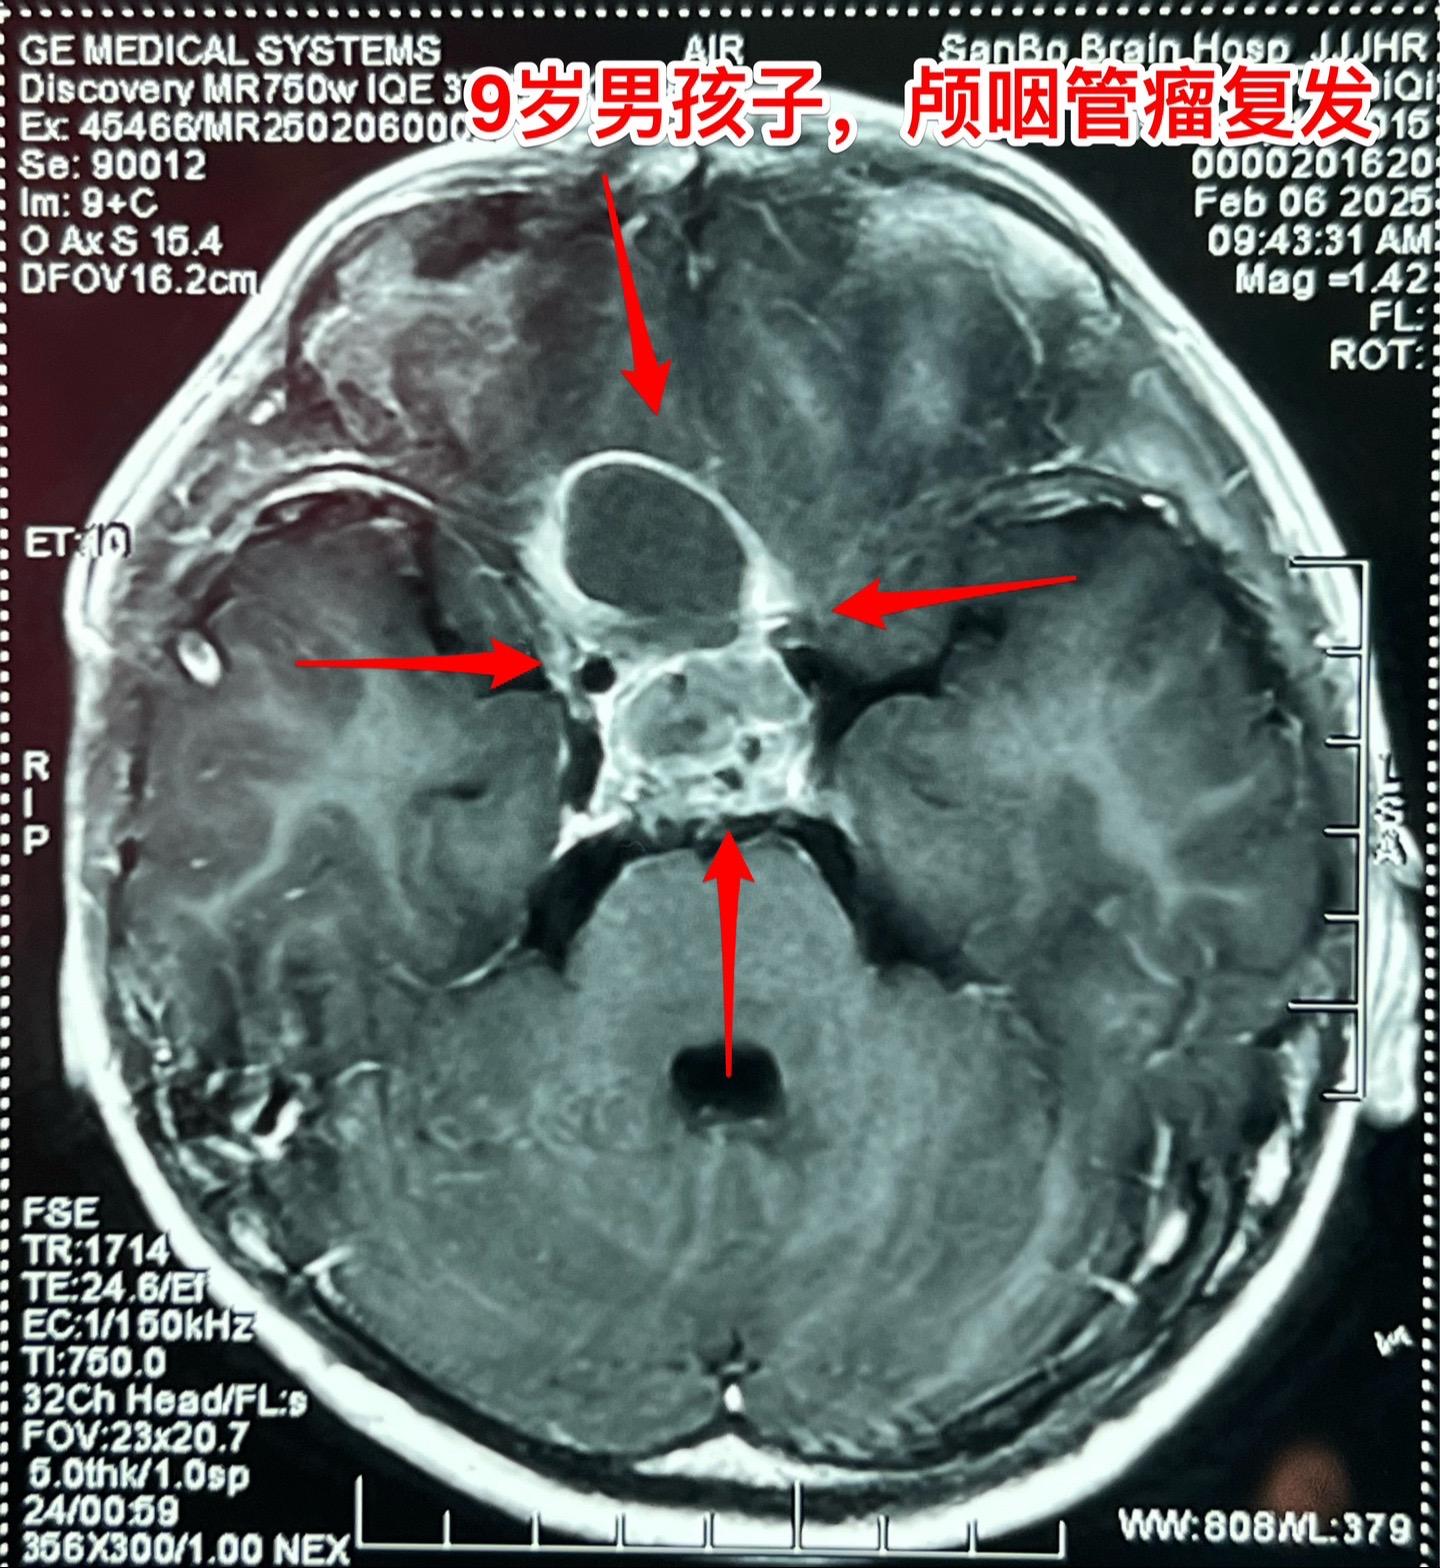

九岁男孩子颅咽管瘤复发,肿瘤生长快。南阳市男孩子2年半前曾经作了一次手术,2024年2月复查磁共振显示垂体窝内无肿瘤复发,鞍背骨质内有可疑异常信号。2025年1月复查磁共振即显示肿瘤复发而且直径达4厘米,患儿家长不敢相信肿瘤居然长得这么快!正月初八患儿即来住院,复查磁共振及CT见图。 病友们经常咨询的问题是肿瘤的生长速度。虽然颅咽管瘤是良性肿瘤,但是不能肯定地说颅咽管瘤的生长速度就很慢。即使在较长时间内肿瘤生长缓慢,也可能在某个时间段出现快速生长,也就是说颅咽管瘤的生长速度不是匀速的,难以预